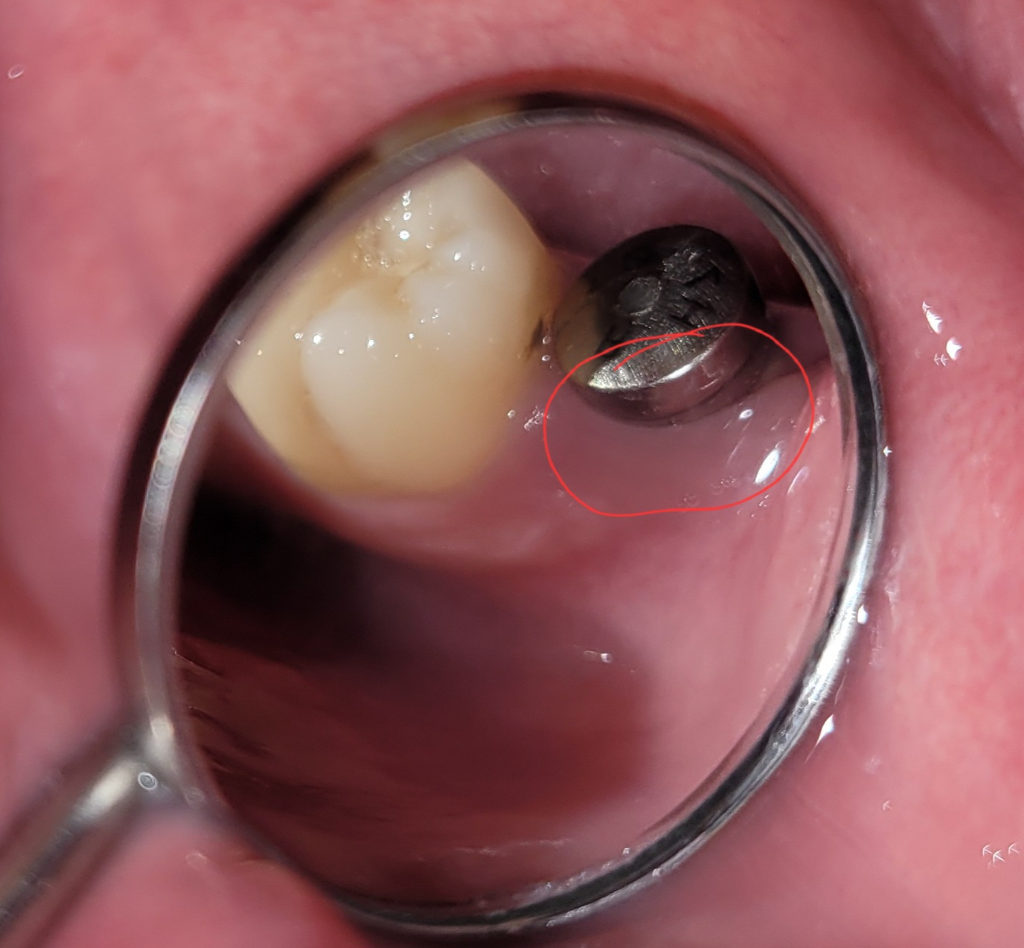

힐링 어버트먼트 주변 잇몸 색이 보라색이에요

사진에 빨간 동그라미처럼 색이 약간 푸르스름 한데 원래 이런가요? 은색에 비쳐서 그런가 싶기도 합니다..

그리고 저부분을 누르면 살짝 아파요

사진상으로 보면 크게 문제가 있어 보이진 않습니다. 힐링에 반사되서 그렇게 색이 보이는거 같습니다.